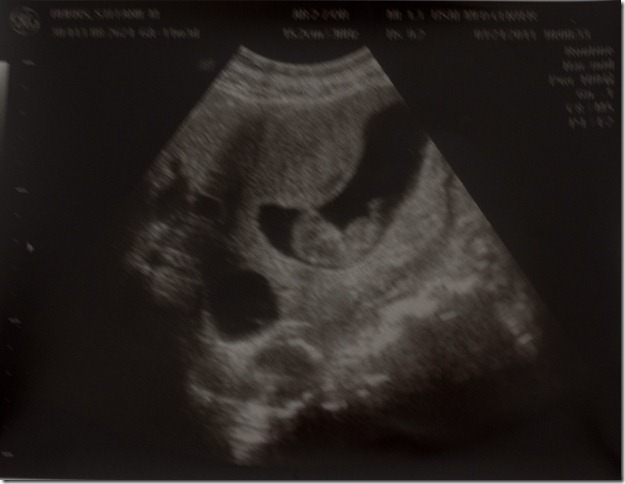

A beautiful sight!

Yesterday morning I had my first ultrasound and here’s what I saw!  It’s always a little nerve-racking going in for that first ultrasound, hoping that everything is alright.  But we could immediately see a little brother our sister bouncing around all over the place with a strong heart beat.  We are very thankful that the Lord has chosen to give us another little baby to raise and we can’t wait to meet him (or her) in August!